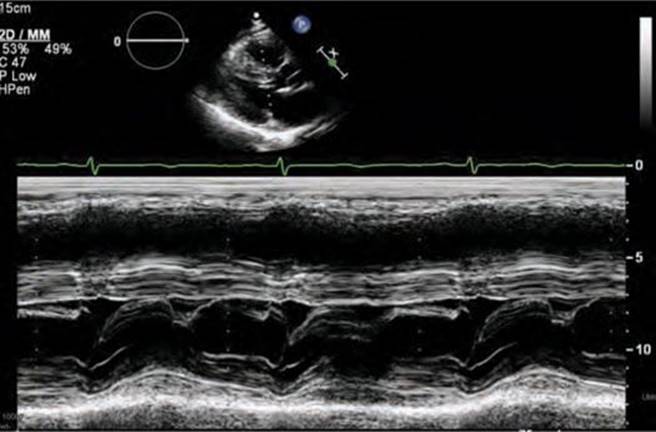

FIGURE 53-5 M-mode across the mitral valve demonstrating SAM with mitral-septal contact.

Screening with transthoracic echocardiogram should be performed at the time of the initial evaluation and yearly thereafter in known HCM patients and is recommended at the time of initial screening of first-degree relatives to assess left ventricular systolic and diastolic function, wall thickness, and outflow tract gradients.1-3,5 The obstruction that occurs in HCM has been shown to be due to mitral valve systolic anterior motion (SAM) with mitral-septal contact (best illustrated in Figures 53-5 and 53-7B), muscular obstruction in the midcavitary region, or anomalous papillary muscle insertion into the anterior mitral leaflet.1,2,6 The peak LVOT or midcavitary gradient should be measured at rest, and if <50 mm Hg, the test should be repeated with provocative measures such as exercise, Valsalva maneuver, or potentially amyl nitrate, with the latter rarely required in the current era. Provocation with dobutamine infusion during echo is no longer recommended. Upon testing, one-third of patients will have a resting LVOT gradient >30 mm Hg (obstructive HCM), one-third will have resting gradients <30 mm Hg (nonobstructive HCM), and a final one-third will have normal resting gradients but provoked gradients >30 mm Hg (labile obstruction).1,2,6